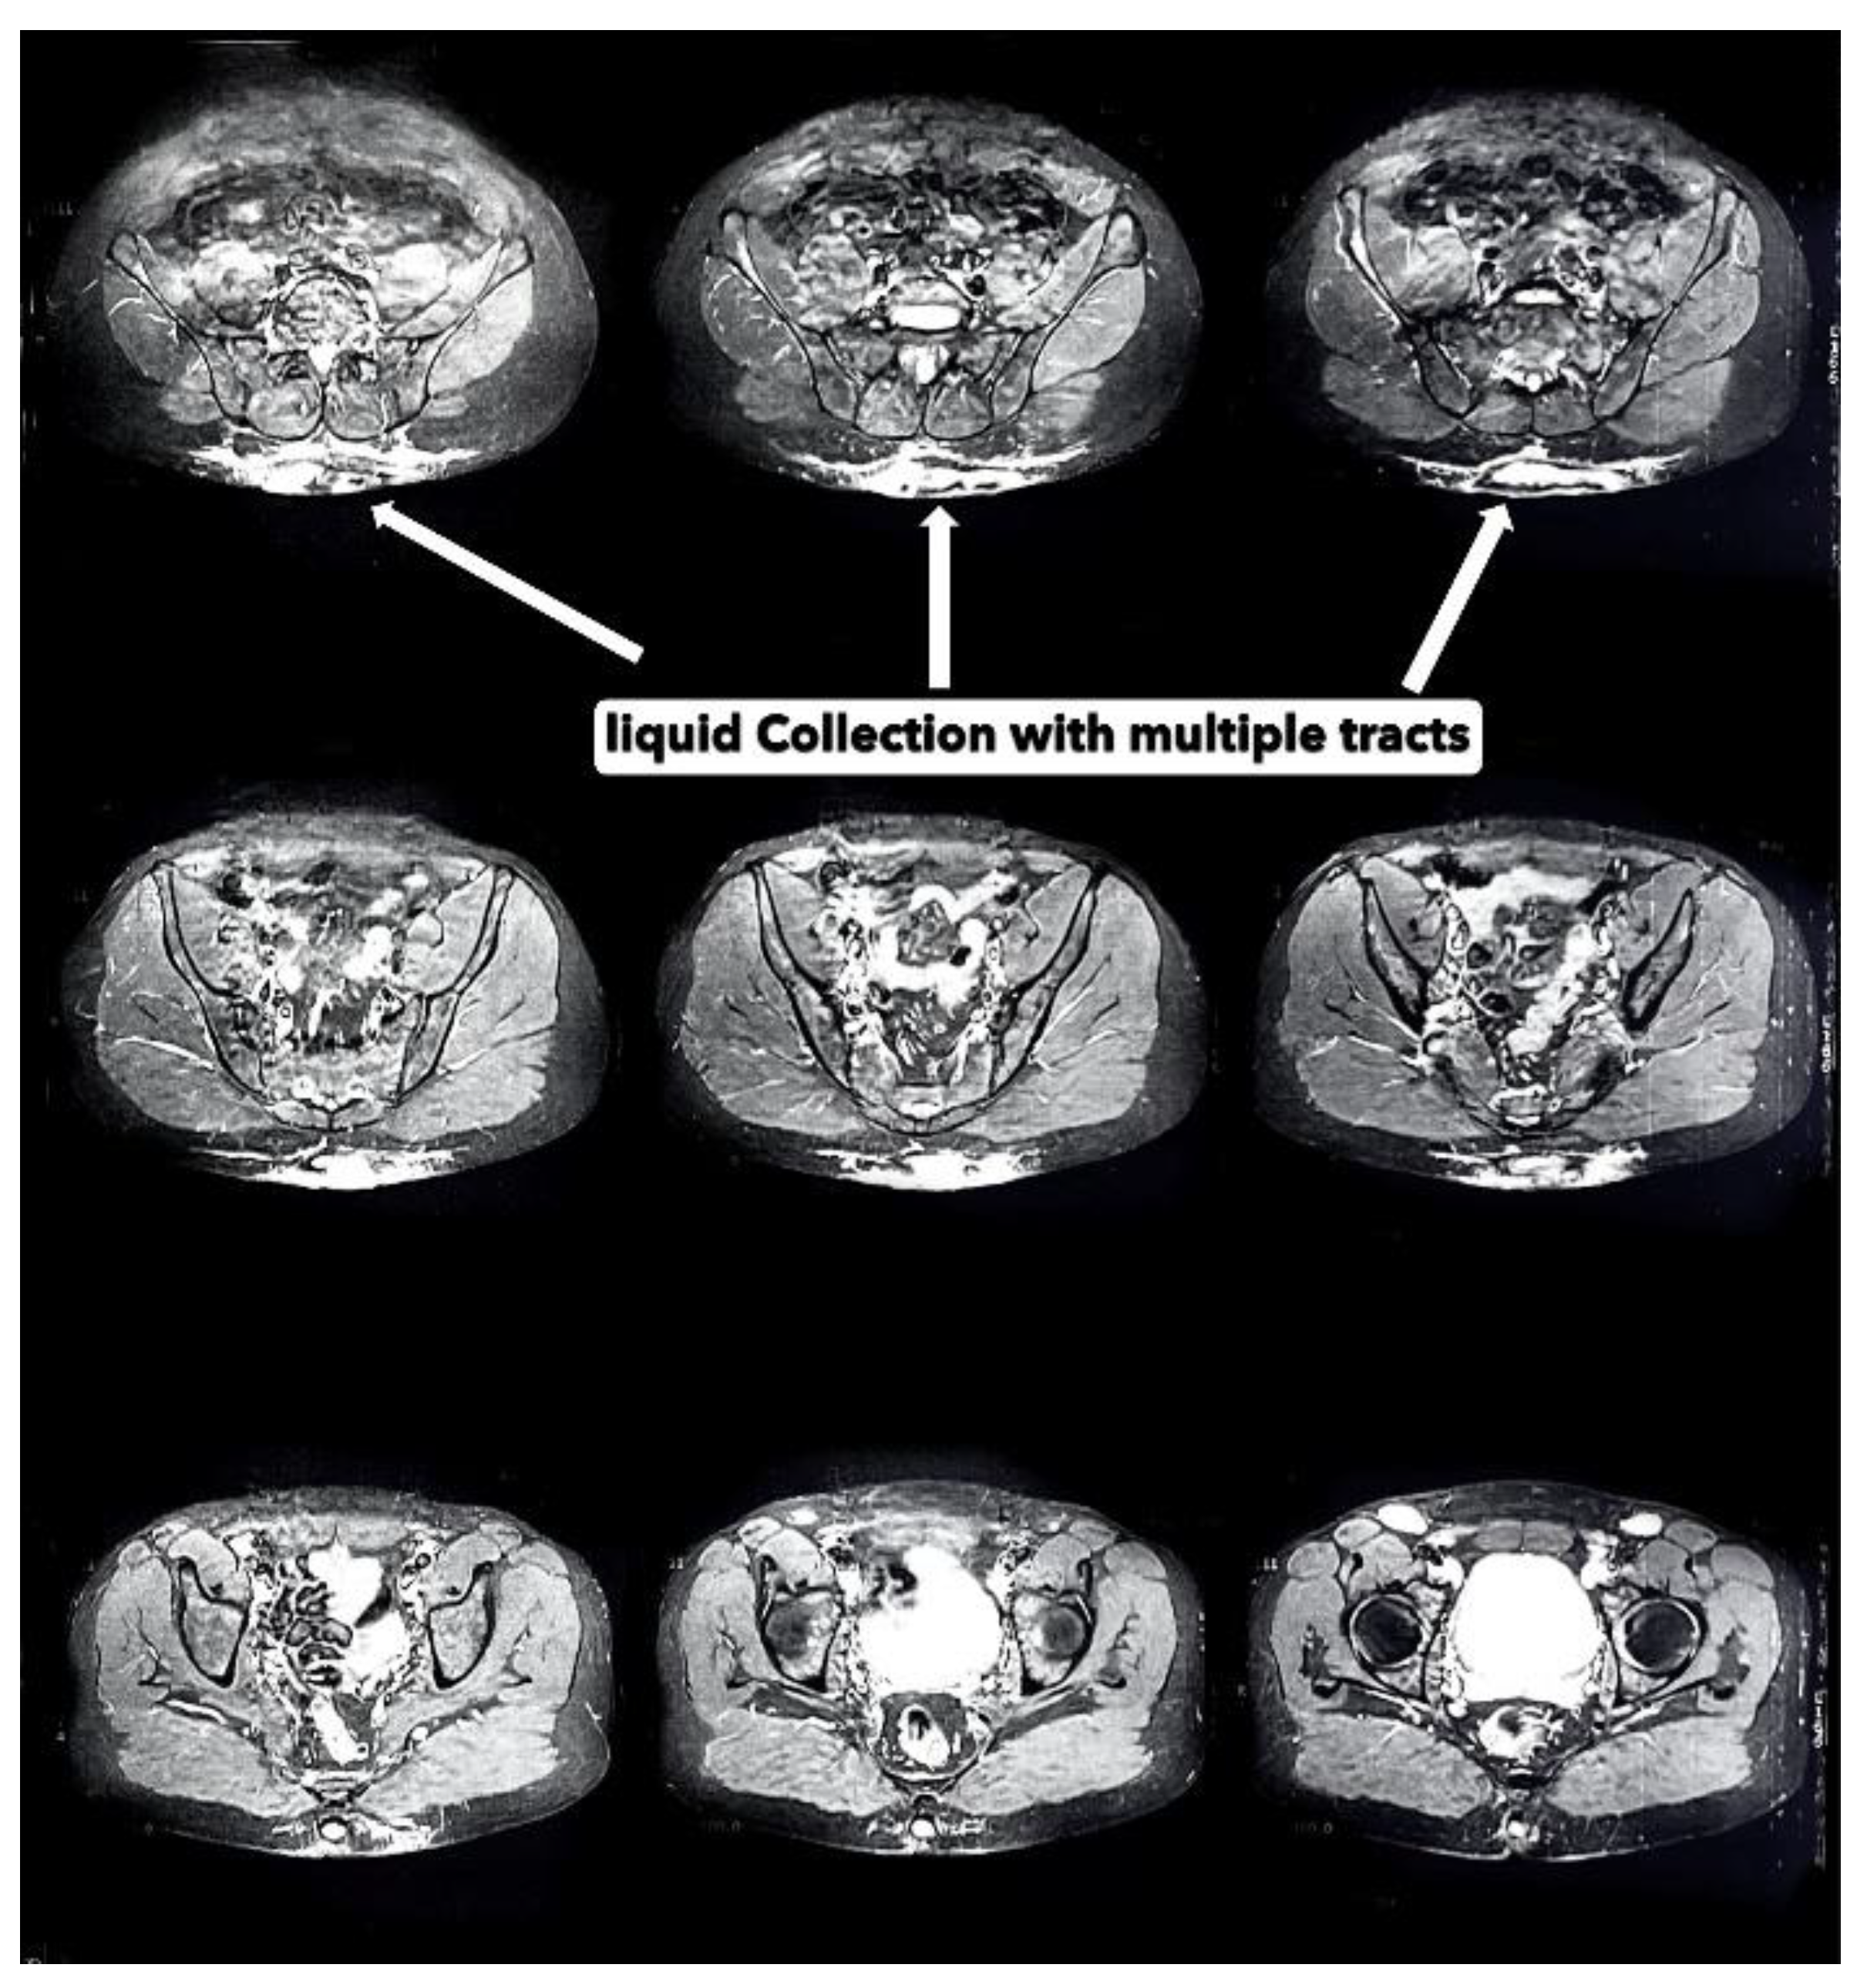

A 34 year old North-African military male, smoker with no past medical or surgery history. With normal BMI of 23. He presented to day-consultation clinic with a good general status, no fever, no jaundice. As the patient reports, the first symptoms appeared 01 year before, through the apparition of lumbar nodule with no other lesion in the arm pits, groin or perineum. The nodule were painful, expanding in volume and number turning to fistulous abscesses over time with purulent discharge causing social disconfort (Figure 1 and Figure 2). Prior to consultation with us, the patient took oral antibiobiotics and some topic antiseptics. The evolution of the lesions motivated a consultation. A clinical evaluation revealed skin ulcers, hyperpigmentation, hardened thick skin folds with orifices discharging pus in the lumbosacral region. Serologic testing for human immunodeficiency virus (HIV), syphilis, chronic infection with hepatitis viruses B and V, as well as chlamydia trachomatis were negative. A computer tomography (CT) imaging concluded with highlighting a polylobed collection associated with multiple fistulous tracts in the subcutaneous soft tissues of the sacrococcygeal region with liquid content showing significant hypersignal on T2 and with a thick wall enhanced after gadolinium injection measuring 20X95X130 mm (Figure 3). There was also soft tissue edema infiltration around the lesion. After the preanesthetic labtest, surgical treatment began. He was placed in ventral decubitus with rachianesthesia. We proceeded with extensive excision of the lesion until presacral fascia in deep with thin (05 mm) normal tissue margin (Figure 4). After careful hemostasis, a sterile dressing was made. The patient was discharged with change of the dressing every 02 days and seen for routine follow-up. Following the procedure, the patient’s recovery was monitored closely, with particular attention to wound healing and any signs of infection. The surgical specimen revealed in pathology lab suppurative hidradenitis with sinus tracts opening with a brisk surrounding inflammatory infiltrate within the dermis (Figure 5). The patient experienced significant improvement in symptoms, and follow-up visits confirmed the effective resolution of the lesion with no immediate recurrence (Figure 6).

Figure 3. Axial CT Image for evaluation reveals presence of polylobulated collection with multiple fistular tracts in soft tissue at the sacrococcygian region measuring 20 mm deep X95 mm large X130 mm height with perilesional oedemateous inflammation.